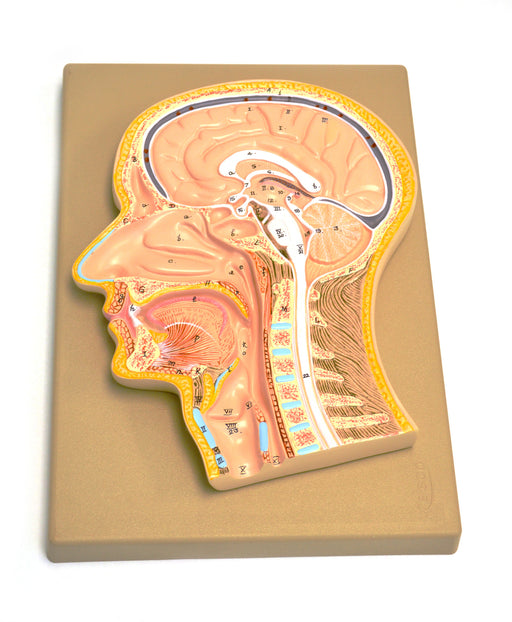

Model, Human, Head, Fontal Section, Median Section

Life Size Median section 12.5"x9"x1" 70 structures identified A two dimensional view of a sagittal section of the anatomy within the human head....

View full detailsAM18AS -